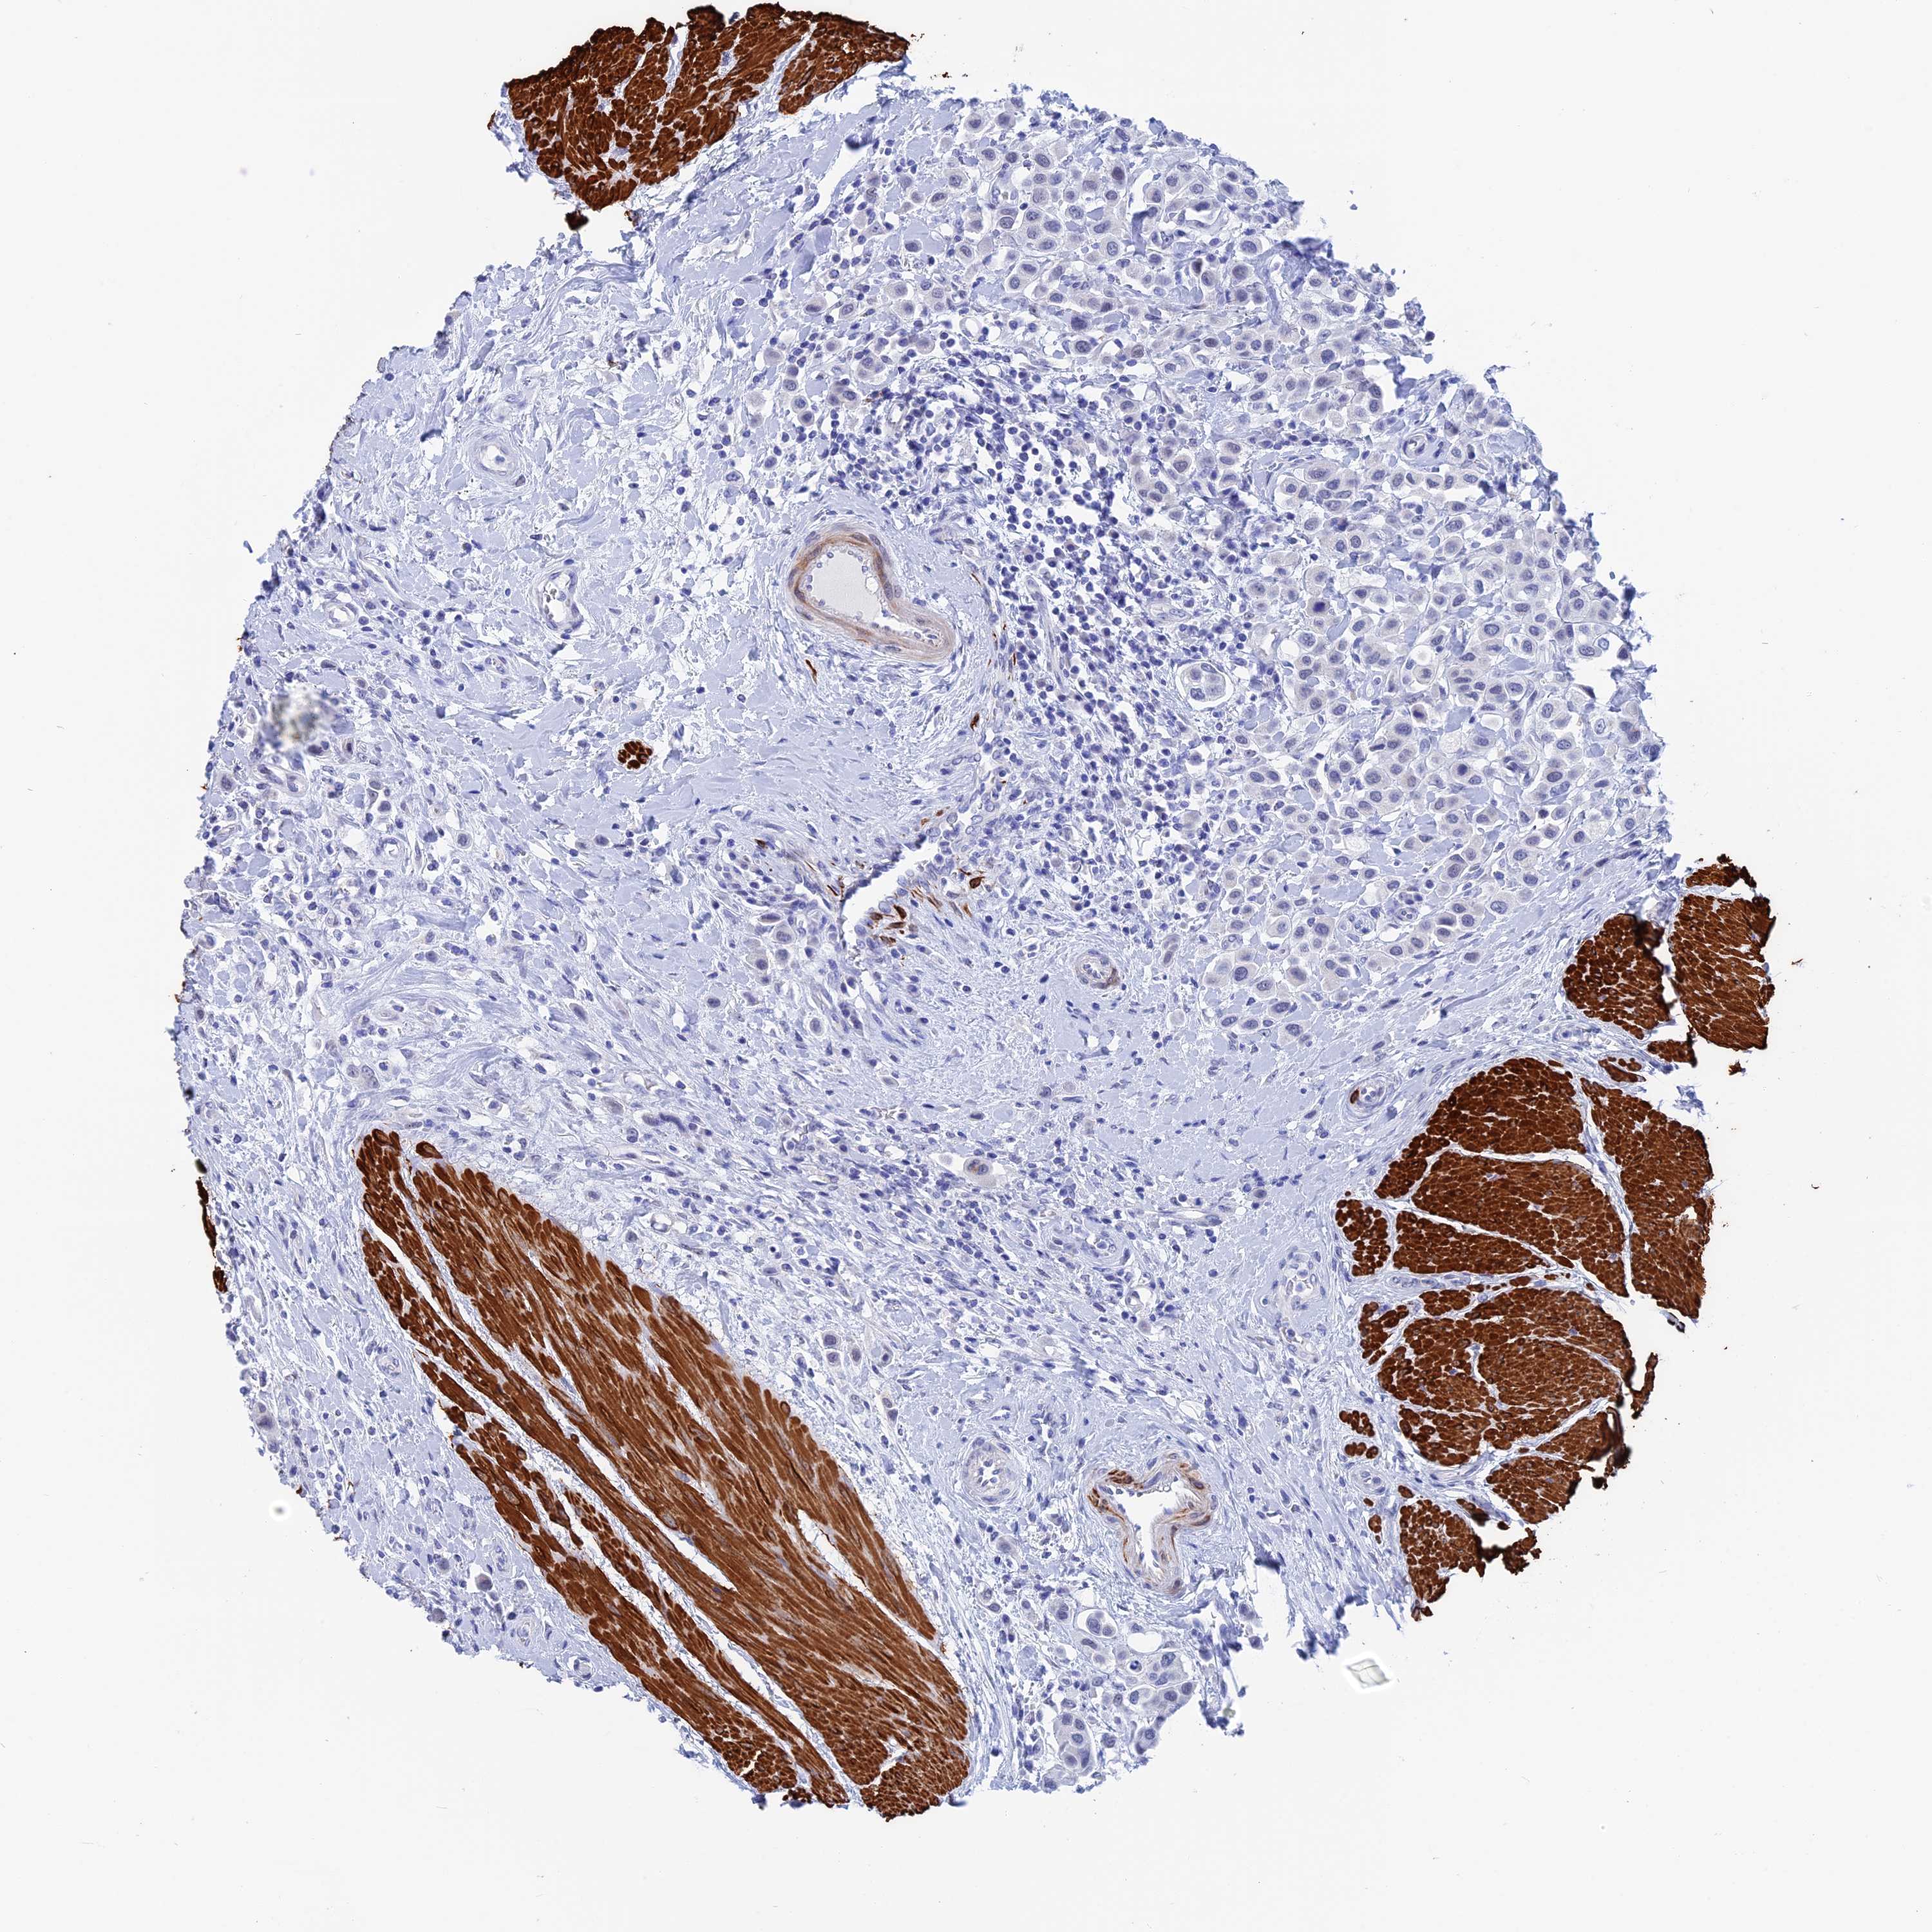

UROTHELIAL CANCER - Protein expressioni

A mouse-over function shows sample information and annotation data. Click on an image to view it in a full screen mode. Samples can be filtered based on level of antibody staining by selecting one or several of the following categories: high, medium, low and not detected. The assay and annotation is described here.

Antibody stainingi

Antibody staining in the annotated cell types in the current human tissue is reported as not detected, low, medium, or high, based on conventional immunohistochemistry profiling in selected tissues. This score is based on the combination of the staining intensity and fraction of stained cells.

Each image is clickable and will lead to virtual microscopy that enables deeper exploration of all samples and also displays staining intensity scores, fraction scores and subcellular localization as well as patient and tissue information for each sample.

Antibody HPA042629

Antibody HPA042838

Urothelial carcinoma, High grade

Urothelial carcinoma, Low grade